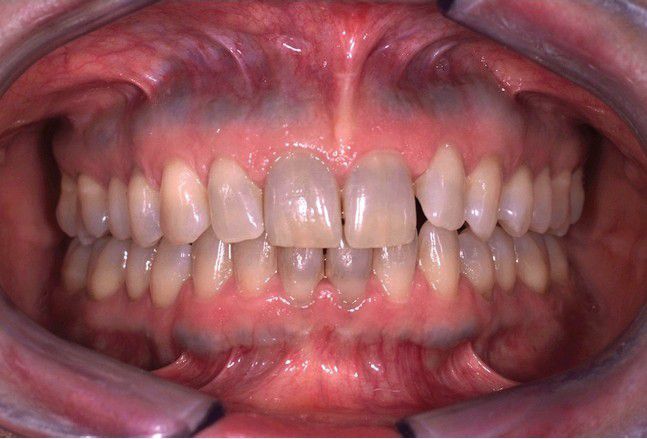

Minocycline related discolouration

Dentition demonstrating grayish discoloration predominantly noted on the incisal half of the teeth. Note the horizontal bands of bluish alteration of the maxillary and mandibular alveolar ridges.